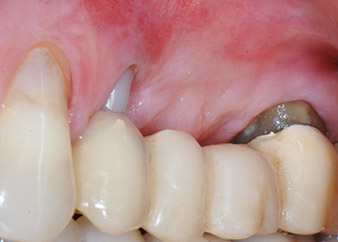

Zwischenergebnis nach zwei Monaten

Die Abbildungen 17 und 18 zeigen das klinische Ergebnis zwei Monate nach dem Eingriff. Die nun verminderte Beweglichkeit des Zahns 24 lag bei Miller-Klasse 1 und das Weichgewebe war entzündungsfrei. Um eine neue Infektion zu verhindern und das epitheliale Attachment nicht zu zerstören, wurde auf eine Sondierung zu diesem Zeitpunkt verzichtet. Die nächste Untersuchung sollte bei der Freilegung und dem Verschrauben der Gingivaformer stattfinden, sechs Monate nach dem Einsetzen der Implantate.

Zwei Monate nach dem Eingriff ist die Patientin schmerzfrei.

Abb. 17: Zwei Monate nach dem Eingriff ist die Patientin schmerzfrei und der Bereich weist keine Entzündungen auf.

Nach dem Eingriff

Abb. 18: Zahn 24 zeigt eine verminderte Beweglichkeit.

Schon bei der Kontrolle zwei Monate nach Implantation hatte sich die Beweglichkeit des verbliebenen „Zahnelements“ 24 von Miller-Klasse 2 zu Klasse 1 verringert. Das weichgewebige Attachment entsprach dem des benachbarten Zahns 23. Die Prognose muss möglicherweise bei der Freilegung angepasst werden, da keine weiteren endodontischen oder parodontalen Symptome vorlagen. Da allerdings fast der gesamte bukkale und approximale Knochen fehlen und der Stumpfaufbau bis zum apikalen Wurzelabschnitt reicht, ist aufgrund biologischer Faktoren kein höheres Attachmentniveau mehr zu erwarten (Sculean et al., 2008).